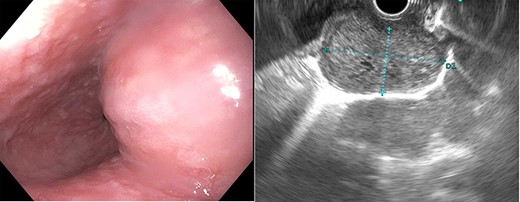

The patient is a 67-year-old male with a history of atrial fibrillation and hyperlipidemia who presented with several months of dysphagia to solids. The endoscopic evaluation revealed a ~4 × 2.3 cm submucosal lesion arising from the muscularis propria in the distal esophagus (Fig. 1). The lesion was 2 cm proximal to the GE junction and intermittently disappearing with peristaltic contractions. The lesion was biopsied and showed low-grade GIST with 1–3 mitoses per high power field and was CD 117 positive. Computerized tomography (CT) scan showed a right esophageal mass without evidence of local invasion (Fig. 2).

Computerized tomography (CT) demonstrated a right distal esophageal mass.